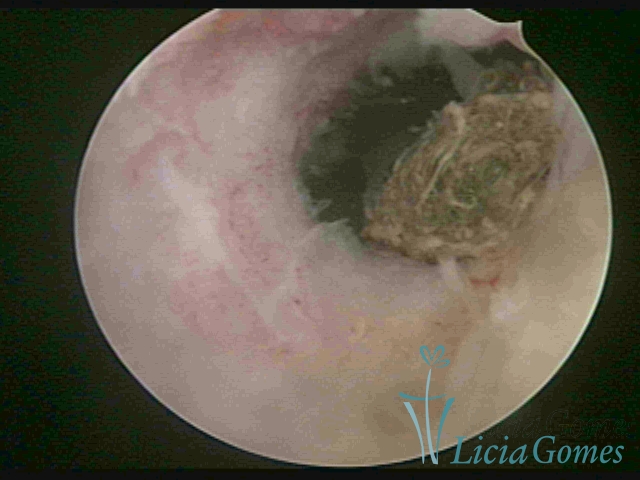

Cavidade uterina com DIU, envelhecido e dobrado